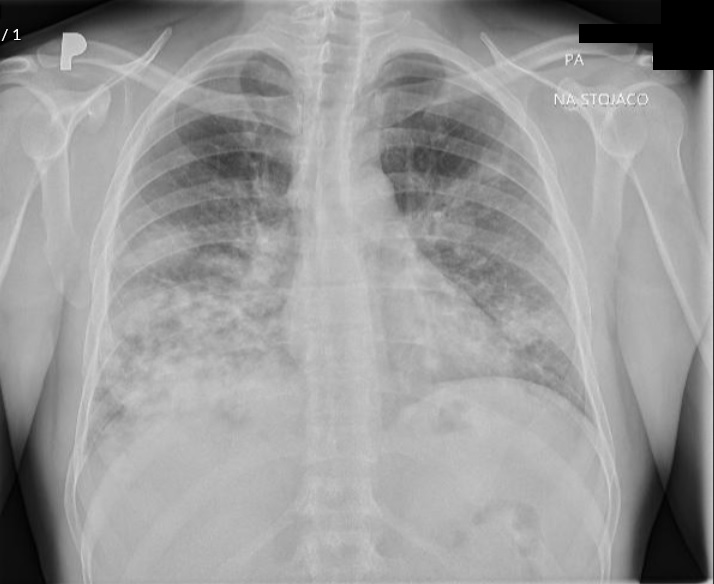

Introduction: This case report describes a serious complication of delayed human immunodeficiency virus (HIV) diagnosis in a patient initially misdiagnosed with palliative-stage cancer and subsequently diagnosed with B-cell lymphoma. This situation highlights the diagnostic challenges and treatment implications following HIV diagnosis, and underscores the critical importance of accurate and timely HIV detection in oncology patients.

Case presentation: A 39-year-old man was initially diagnosed with lung cancer based on computed tomography and histopathologic findings. He was treated with 2 lines of chemotherapy over an 8-month period, the neoplastic lung lesions progressed, and he was referred to palliative care. Two years after his initial diagnosis, during the management of an actively bleeding gastric tumor, he was diagnosed with HIV and referred to an infectious disease unit. Immediate antiretroviral treatment was initiated after diagnosis, and further evaluation confirmed the presence of B-cell lymphoma. A retrospective review suggested that the initial cancer diagnosis was likely misinterpreted and was in fact lymphoma, a malignancy commonly associated with HIV. Lymphoma treatment was initiated, and after 1 year, the patient achieved HIV-1 virologic suppression and near-complete remission of all lesions.